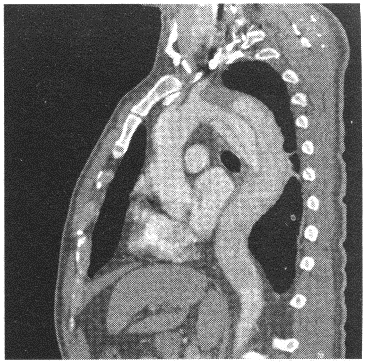

患者,女性,50歲。胸背部疼痛1天余。查體:呼吸音減弱。胸部CT強化如圖。

19.CT圖片顯示的征象包括

20.最可能的CT診斷是

21.顯示主動脈夾層破口位置的最佳CT后處理方法是

正確答案:19.CDF;20.B;21.C